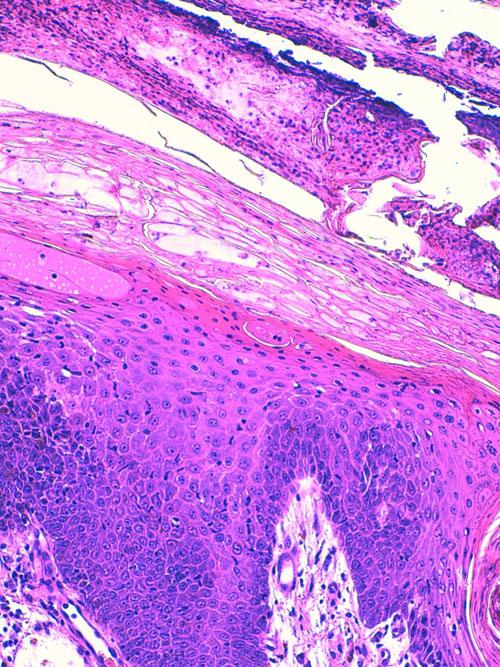

L’examen histologique (LAPVSO, Frédérique DEGORCE) décrit une hyperkératose parakératosique intense constituant une couche cornée épaisse et compacte. Des foyers d’acanthocytes vacuolisés et oedémateux sont présents avec scission de l’épiderme à leur niveau. Une exocytose transépidermique modérée de lymphocytes et neutrophiles est présente, sans images de satelllitose. Le derme est peu inflammatoire, oedémateux et congestionné. Sur certaines biopsies, les lésions ulcérées et vésico-pustuleuses prédominent au sein de la couche cornée. L’examen confirme l’hypothèse d’érythème nécrolytique migrant avec complication de pyodermite supeficielle impétiginée. (photos)

Photos 9 et 10 : Lésions cutanées